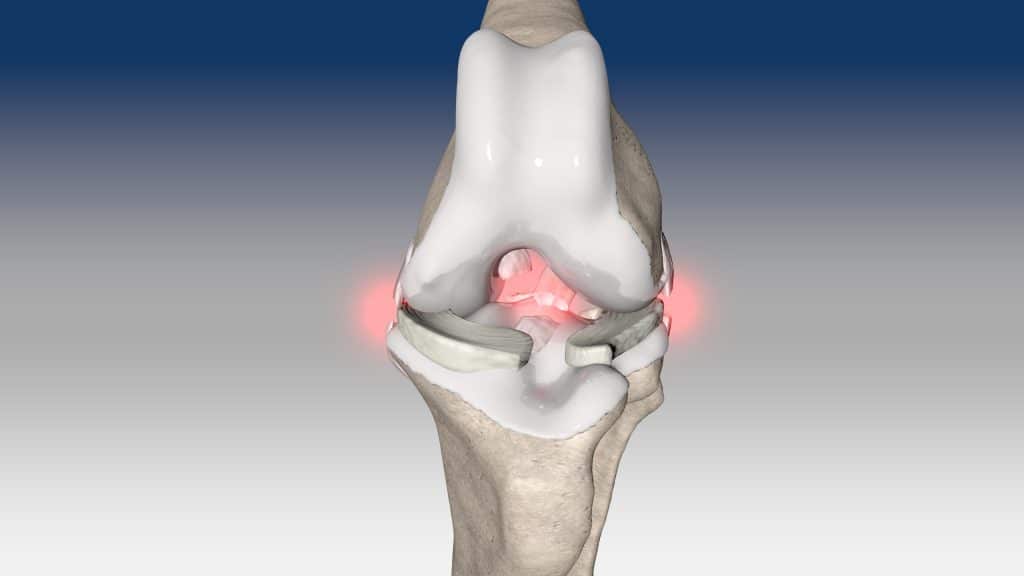

V případě zkřížených vazů umožňuje intraartikulární rekonstrukci v izometrických bodech připojení, čímž obnovuje biomechaniku kolene a všechny funkce natrženého vazu.

V případě více vazů kolene (kraniální, kaudální, kolaterální) je možné pomocí NOVALIG® anatomicky rekonstruovat každý vaz.